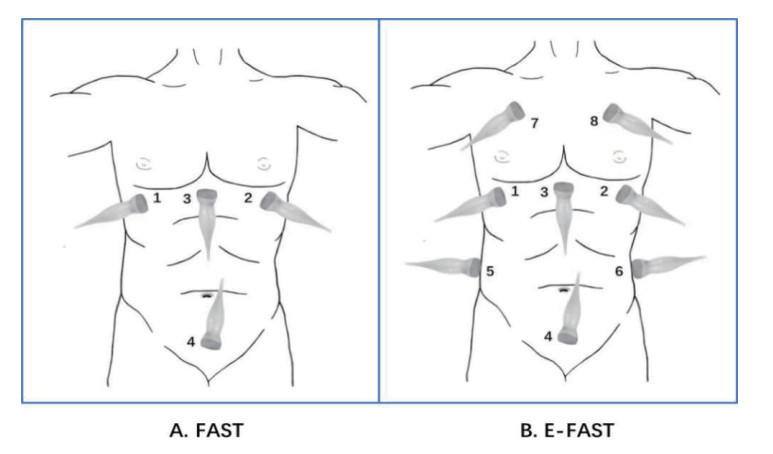

1 载人航天可能发生的伤病及超声应用 1.1 航天员返回可能伤病情在过去的60多年中,载人航天曾先后发生过多种安全事故和故障,造成多人死亡,以发动机故障、起火、推进剂泄露等引发的烧伤、中毒、冲击伤多见[7]。在载人航天飞行中,航天员在发射、在轨飞行期间、返回舱着陆中都可能发生伤情,有的与机械故障相关,有的与航天员自身适应性相关。结合既往航天事故及多次执行神舟载人飞船任务的实际经验,预期可能出现十余种伤病情[8],包括冲击过载伤、推进剂中毒、颅脑损伤、骨折、胸腹伤、失血性休克、烧伤、减压病、航天运动病等。航天冲击过载伤可能会发生在以下场合:火箭发射前紧急救生“0”高度逃逸时的加速度过载、火箭分离、船-箭分离-返回舱与轨道舱分离、降落伞开伞即刻、以及返回舱着陆瞬间,都可能会发生冲击过载伤。冲击伤往往外轻内重,累及多个脏器,发展迅速,容易漏诊。FAST早期主要针对腹部创伤检查,可以快速发现肝周、脾周、盆腔等腹腔内积液。对于钝性腹部损伤,尤其合并低血容量时,常规临床检查敏感度较低,而FAST的阳性检测敏感度可达100%[9-10]。随着临床实践不断应用和发展,FAST应用扩展到了对胸肺部,逐渐演变为E-FAST。E-FAST对于血气胸的敏感度显著高于胸片,与胸部CT结果具有一致性[11]。FAST或E-FAST的超声应用,可以对胸腹腔重要脏器进行快速排查,及时发现如钝性腹部创伤、血气胸等隐匿伤情。

⑵后送载体平台救治,航天救护中所用后送载体主要为直升机和地面医监医救车,直升机是航天医疗救护的首选载体。如遇特殊地形或极端天气,直升机不能起飞或无法降落,医监医救车可第一时间进入现场展开救治运送。直升机作为重要的战场急救医疗救护的载体之一,转送速度快,受地形影响小,在野战医疗急救中发挥了重要作用,直升机医疗急救体系(helicopter emergency medical services, HEMS)在降低创伤患者病死率方面与地面医疗急救体系(ground emergency medical services, GEMS)疗效一致,但比地面救治转运距离更远[13],从而为伤情的急救及后送赢得了宝贵的时间,已成为空间站任务院前急救中的主体。但直升机内强大的噪声,不利于临床医生进行常规心肺听诊等物理检查,因此近几年提出了直升机重点超声检查(point-of-care ultrasound, PoCUS)概念[14],即以直升机作为急救平台,在直升机上进行快速且有针对性的超声探查,研究显示在直升机上所获得的超声影像的质量并不劣于地面救治[15]。故在后送载体内运用FAST或E-FAST的快速筛查法,可行性强,是快速发现如钝性腹部创伤、血气胸等一些引起的血流动力学不稳定的隐匿伤情的可靠方法[16],为院前救治(图 1)赢得宝贵时间。

检查方法:患者取平卧位,按顺序探查4个部位(图 10-A):剑突下、左右肋间、肋下和耻骨联合上方快速探查心包、肝肾间隙、脾肾间隙和Douglas窝是否存在积液。每个部位均采用连续性扫查。检查时间一般不超过5 min。

| A:1=右侧肋缘下, 2=左侧肋缘下,3=剑突下,4=耻骨联合;B:1=右侧肋缘下, 2=左侧肋缘下,3=剑突下,4=耻骨联合;5=右侧液后线与肋角交界处,6=左侧液后线与肋角交界处,7=右侧胸前第二肋,8=左侧胸前第二肋 图 10 FAST与E-FAST的检查部位 |

E-FAST是在FAST的基础上进一步深入检查,同时增加了对胸腔(双肺)的评估,即双肺、肝周、脾周、心包、盆腔周围5个部位(图 10-B)。可辅助诊断急性呼吸衰竭和创伤性胸部损伤。其中肺部超声检查部分方法同上。